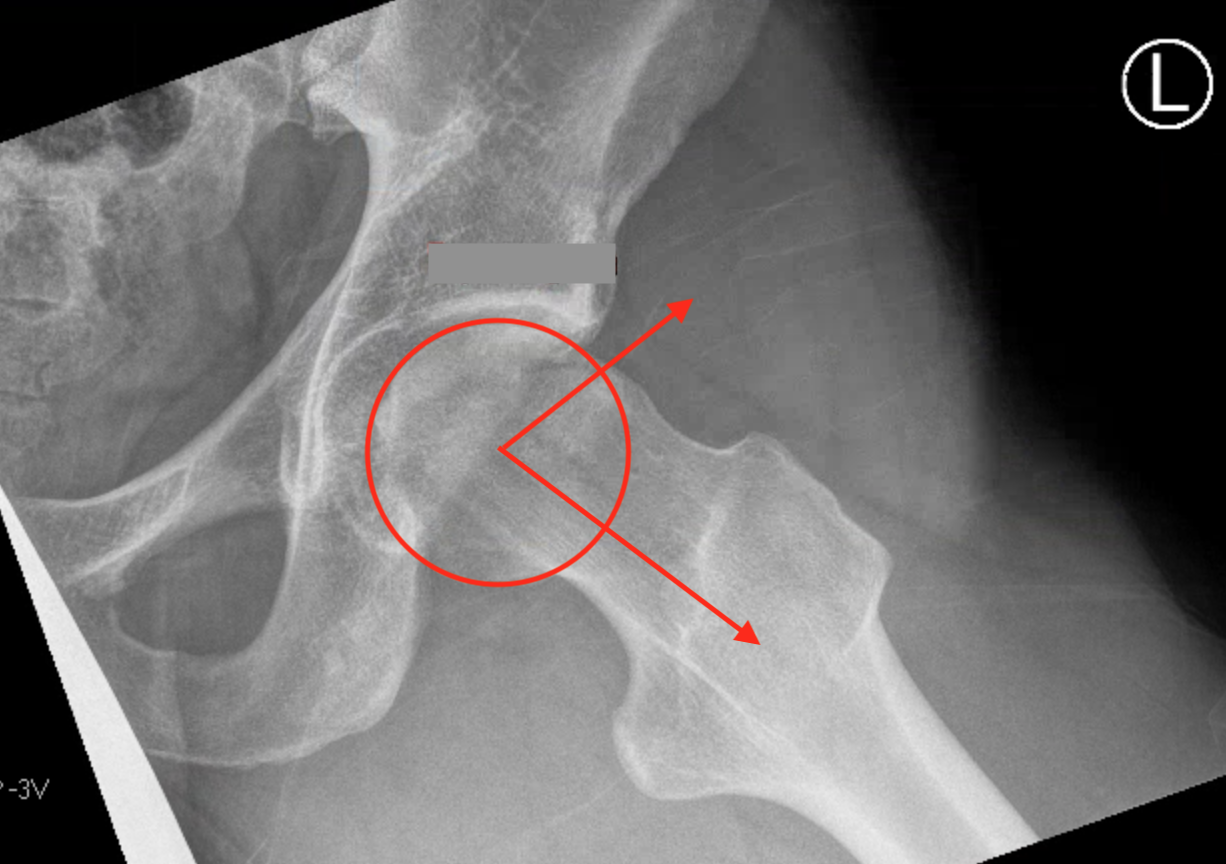

Alpha angle

Measurement

- centered in the center of the femoral head (best fit circle)

- formed by two lines

- one line center of the femoral neck axis

- a line where the femoral head leaves a best-fit circle

- higher alpha angle with Cam lesion

Alpha < 55 degrees Alpha > 55 degrees